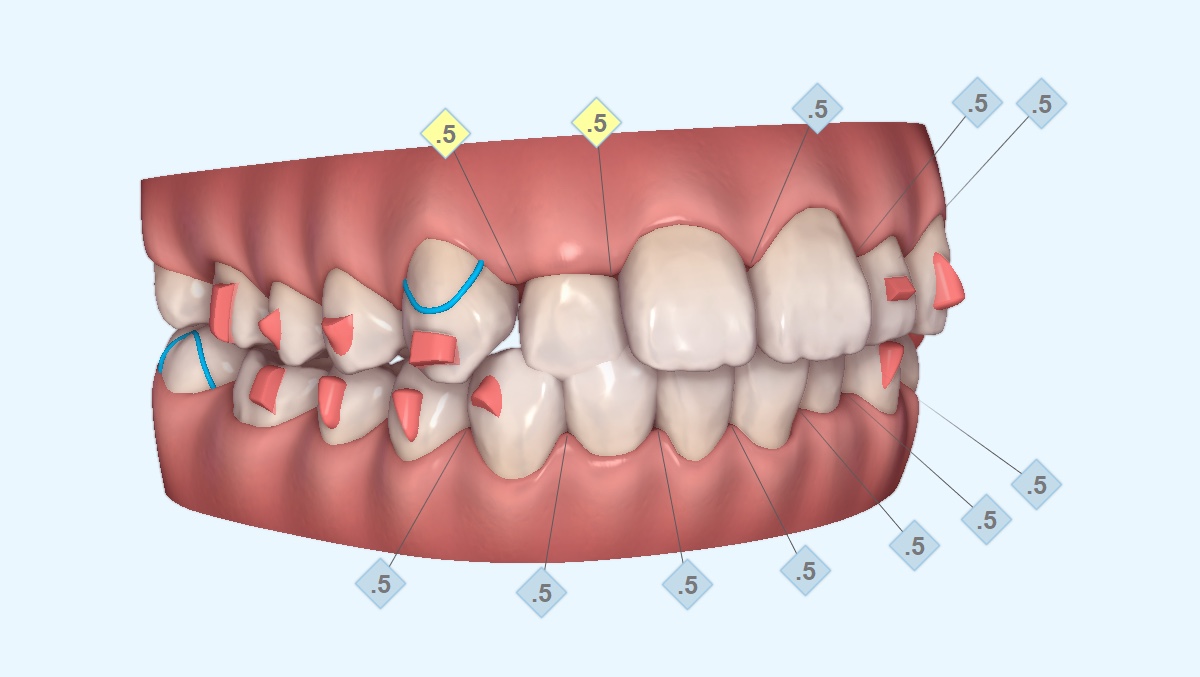

マウスピース矯正は複数枚のマウスピースを交換しながら歯を動かしていきます。AIが設計した計画通り進めると1枚ごとに約3%のズレが生じます。10枚のマウスピースを利用する頃には約30%のズレが生じることになります。つまり、ゴールから30%ズレてしまうということです。

多くのドクターがこのズレに気づかず治療を進め、途中で「おかしいな?」となり、1から治療をやり直すことを繰り返し、最終的には予定の治療期間の何倍もかかることがあります。また、やり直しをせず、歯並びが整っていない段階で治療を終了してしまうドクターもいます。

つまり「AI(人工知能)」に頼りきりの治療は必ず失敗するということです。これを防ぐためには「知識と経験がある担当医による設計への介入」が必須になります。以下で示すのは、同じ症例で「AI主導」と「人主導」の治療期間の比較になります。

同じ症例であっても算出されるマウスピースの数が異なり、治療期間に1年6か月の差が出ました。これがドクターの「質の違い」です。